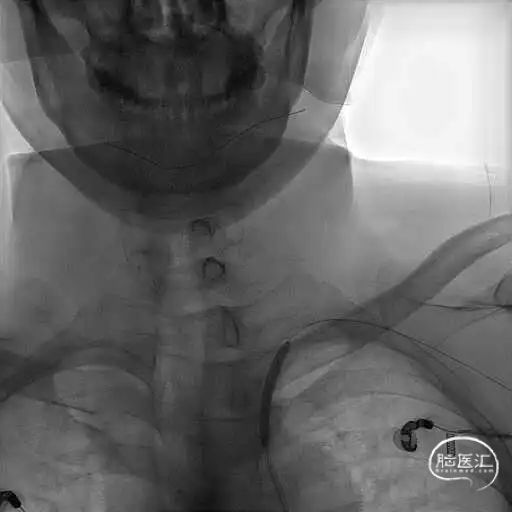

右侧椎动脉造影提示左侧锁骨下动脉盗血,左侧锁骨下动脉闭塞,近端残端较圆钝。

8F Guiding+5F MPA同轴置于左侧锁骨下动脉残端处,反复尝试Command 190cm及Command ES 190cm导丝配合Rebar-18微导管,导丝无法进入真腔,更换Connect 195cm导丝尝试后顺利进入真腔,使用小球囊预扩, Guiding跟到病变远端。